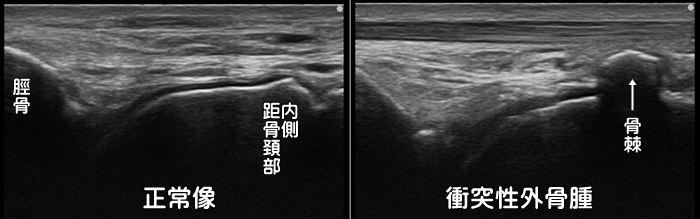

衝突性外骨腫

別名・フットボーラーズアンクルとも呼ばれ、サッカー選手に多い足首前方の痛みを誘発します。多くは足首の捻挫後に関節が緩くなり不安定な状態のままでプレーを続けると骨と骨とが衝突して、その修復過程で骨増殖が起こります。足首の前方の骨に骨棘ができると、それが邪魔になり足首の背屈制限(上に曲げられない)の原因にもなります。